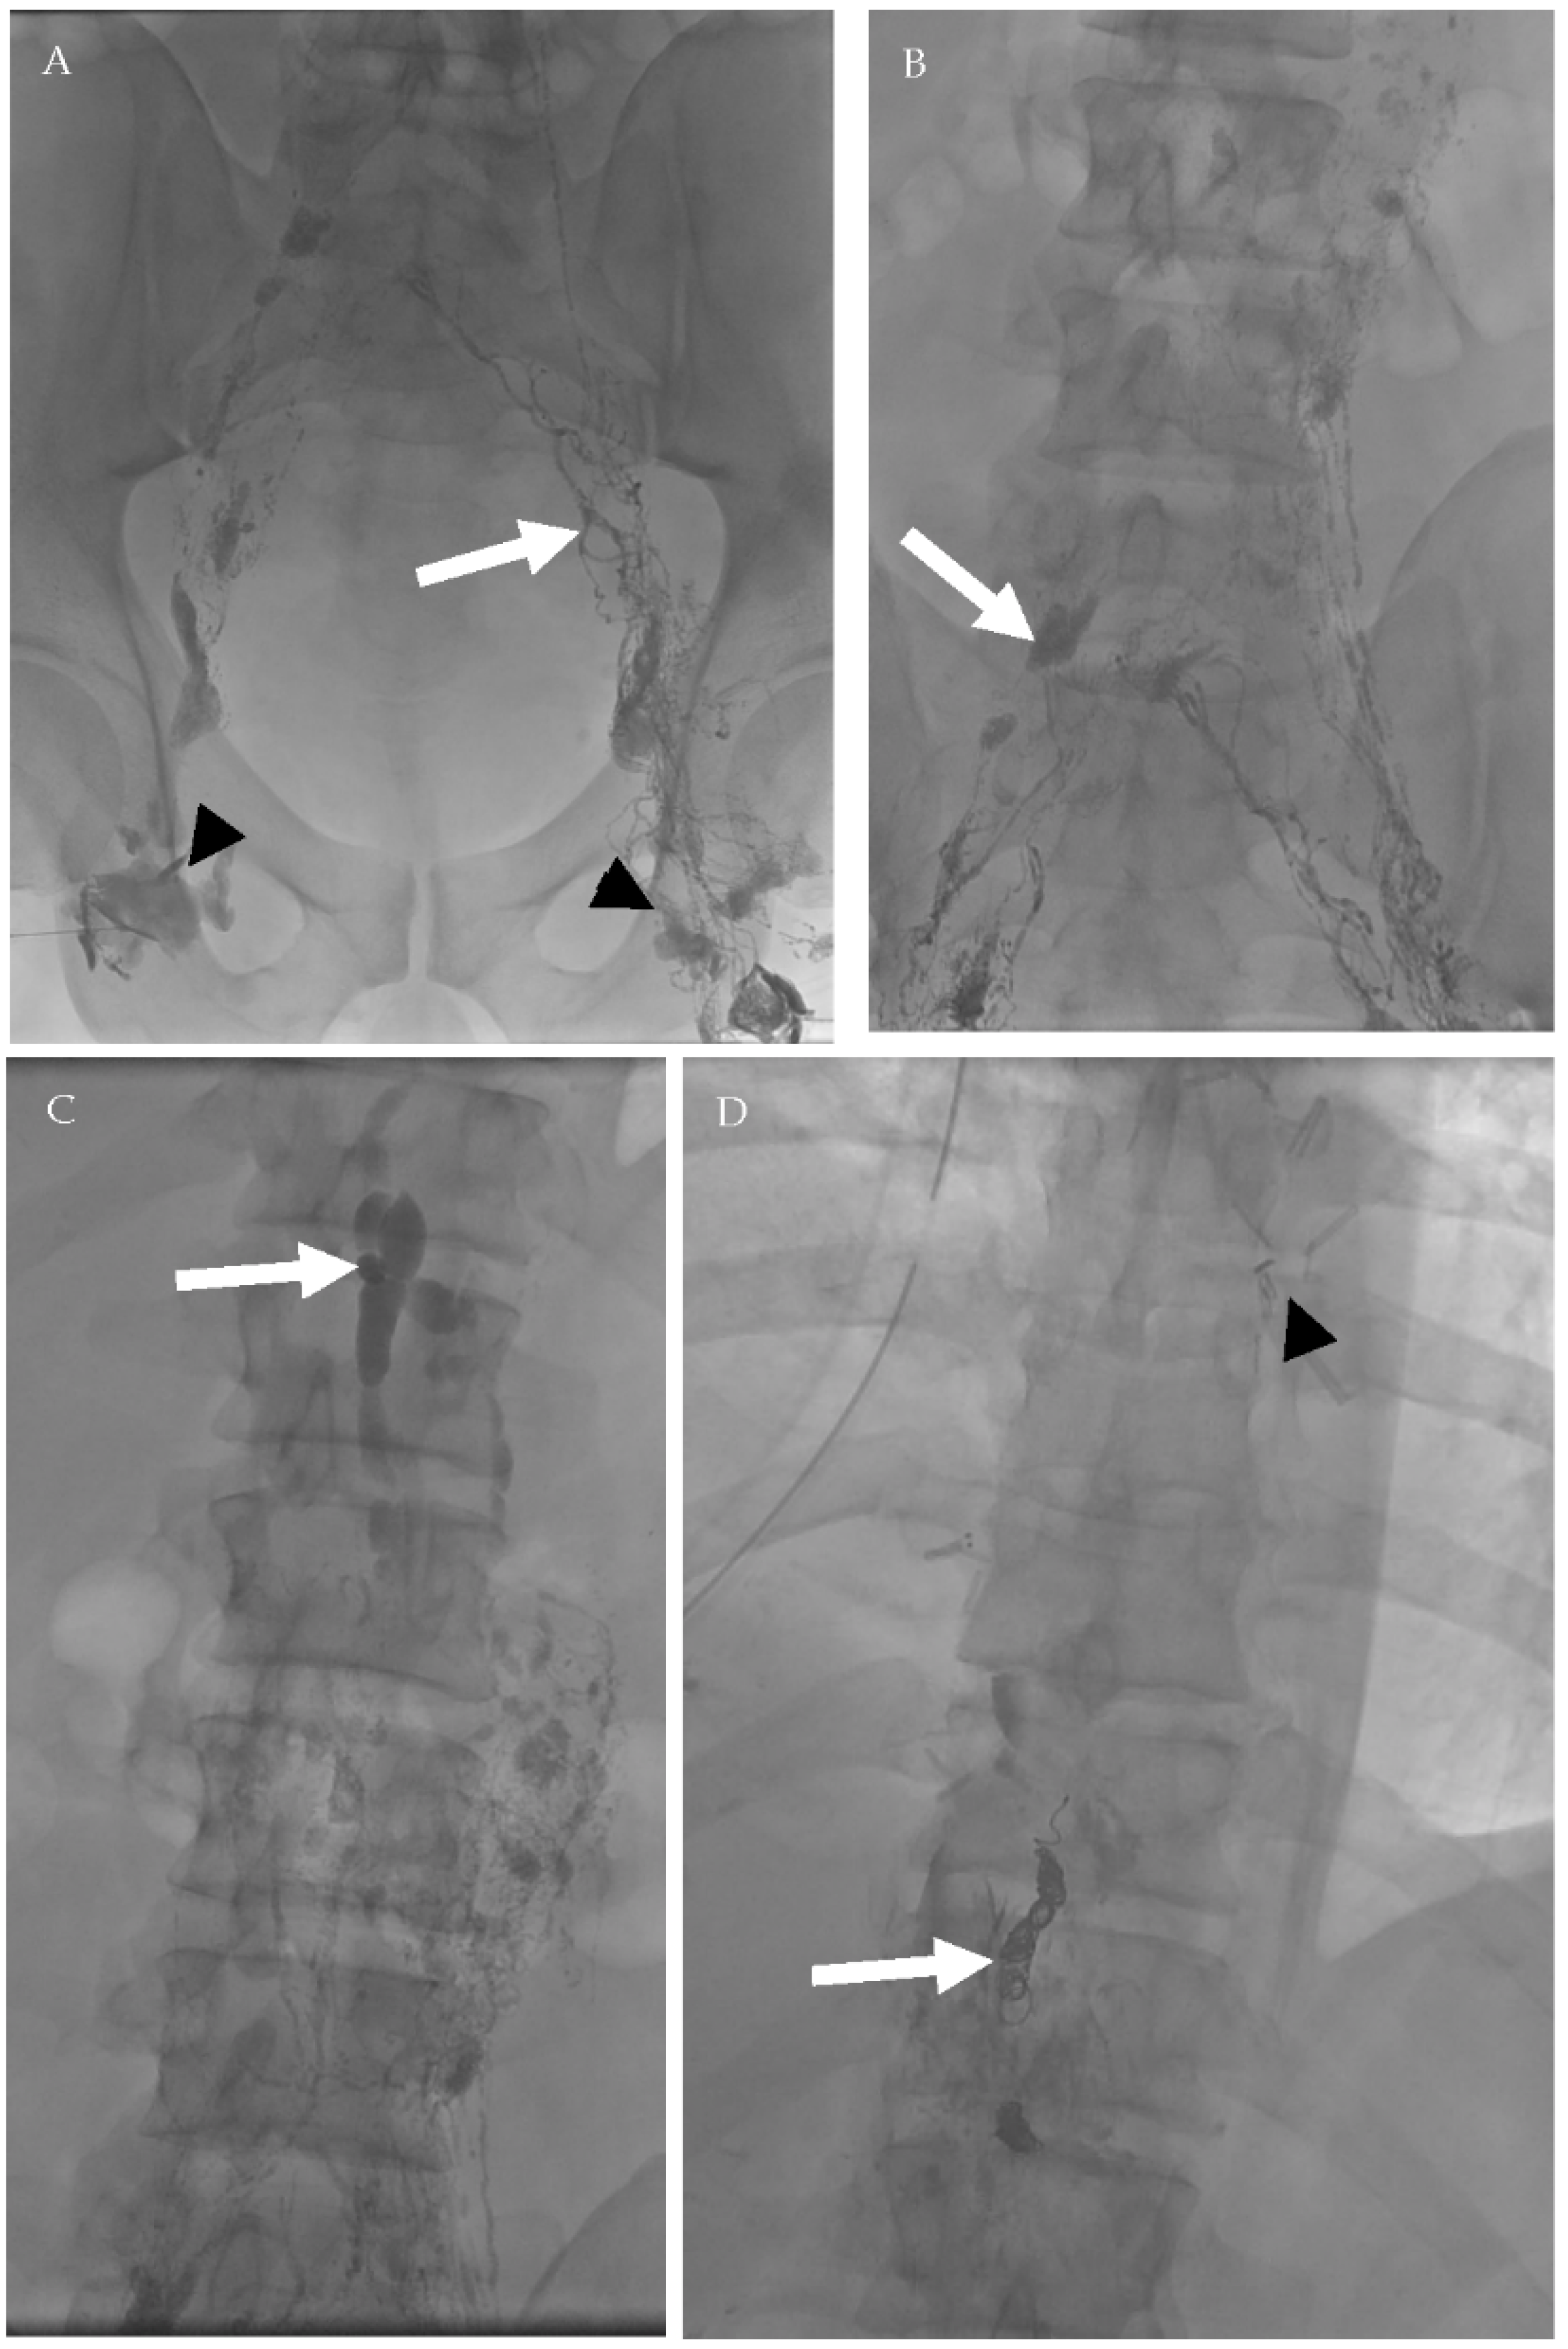

4.2.1. Conventional Lymphangiography (CL)

4.2.2. Magnetic Resonance Lymphangiogram (MRL)